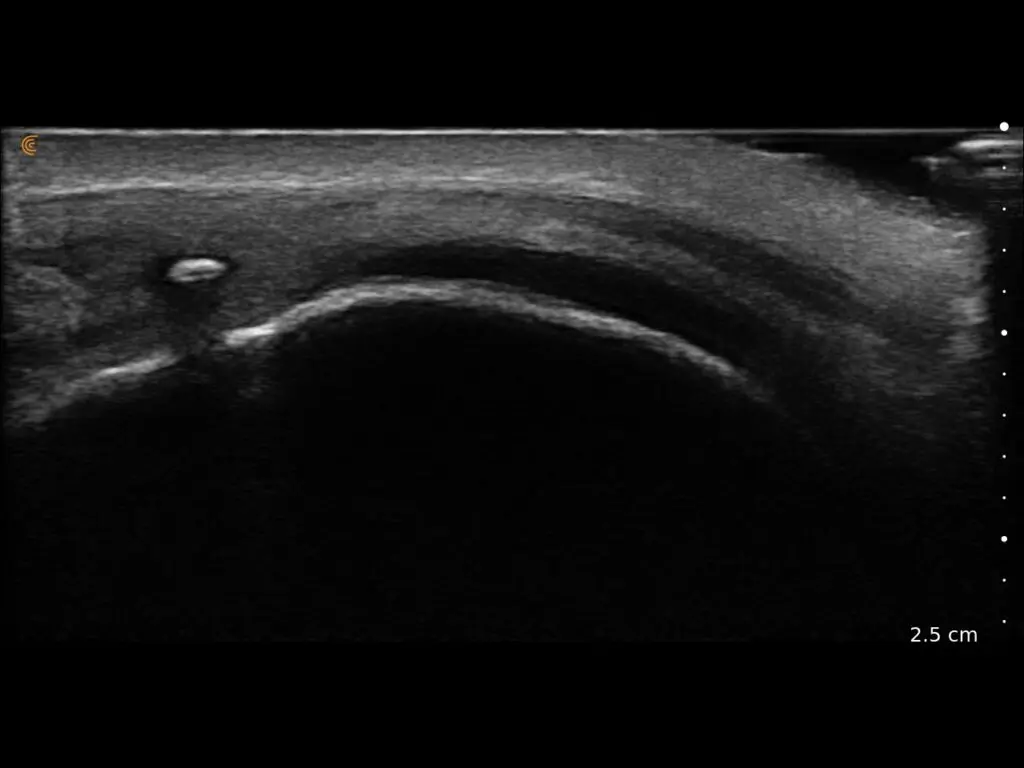

ProbeFix Dynamic is a new device that enables high-quality ultrasound measurements during dynamic exercise by keeping an ultrasound probe in place, allowing for muscle monitoring during intense movement and creating new research possibilities in muscle imaging.